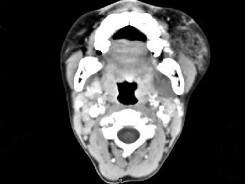

问题 男,12岁,左面颊肿大5年余,局部呈紫红色,CT如图所示,最可能诊断为 ( )

选项 A、慢性腮腺炎 B、下颌下腺慢性炎症 C、血管外皮瘤 D、动静脉畸形 E、蔓状血管瘤

答案 E